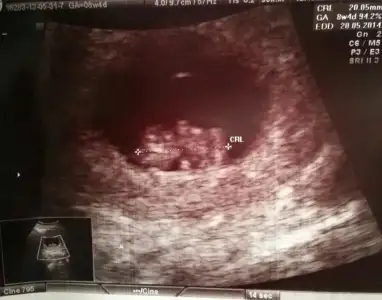

Kızlarr biz kontrolümüzden geldik. Çok şükür herşey yolunda. Ellerimiz kollarımız belli olmaya başlamış. Geçen sefer arada 4 günlük bir fark vardı dah büyük çıkmıştı bebişim. Bu defa sat la aynı çıktı. 8+4 Olmuşuz. 1 Ay sonra tekrar gidicez. Şuana kadar hiç kilo almadığım hatta 2 kilo verdiğim için kızdı doktorum. Bir sonraki gelişine kilo al da gel dedi.Bizden haberler bunlar. Çok şükür bu bayram çifte bayram yaşayacağız.